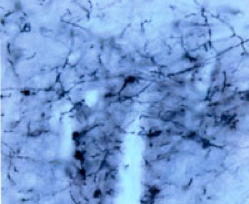

| 成年小鼠腰椎脊髓的Fluoro-Gold(熒光金)染色圖,在跟DAPI復染后,呈現(xiàn)出典型的熒光金柱狀標記 | 伏隔核注射Fluoro-Gold(熒光金)后,用Fluoro-Gold(熒光金)抗體檢測 |

美國 Fluorochorome 公司于1985年成立于美國科羅拉多州丹佛市,F(xiàn)luorochorome一直致力于熒光染料的研究與開發(fā),其專利產品Fluoro Gold(熒光金)自1985年推出以來在全球范圍內被廣泛應用,并有大量的參考文獻。熒光金在紫外線激發(fā)下發(fā)金黃色光,特點是非常靈敏,不僅能標記胞漿,而且能很好地顯示樹突分枝,但核和核仁不染色;在胞體內分解慢,甚至在注射后存活2月標記強度仍無明顯變化;比較耐紫外線的照射,褪色比較慢;可以經受許多組織學染色處理,因而可以和HRP、免疫組織化學等方法結合。同時,F(xiàn)luorochrome公司還開發(fā)了高靈敏度的Fluoro-Gold抗體、以及 Fluoro-Ruby(紅色熒光金)等產品,擴大了其產品的應用范圍